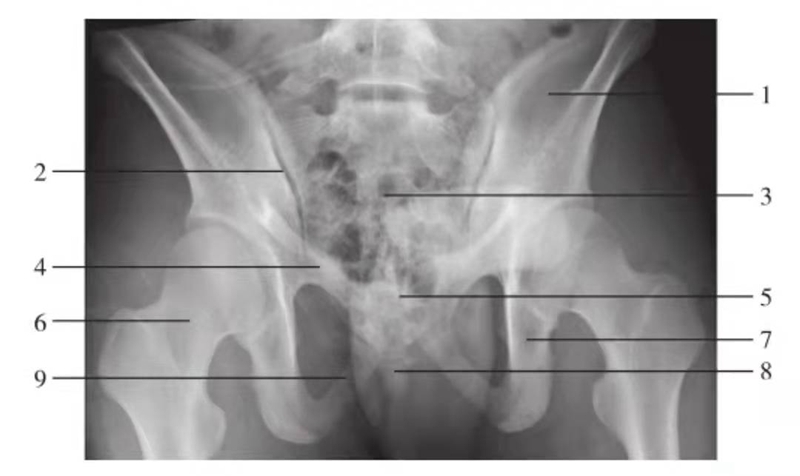

骨盆前后位

图6 骨盆正位

1.髂骨翼;2.骶髂关节;3.髂前下棘;4.髂骨体;5.髋臼顶;6.股骨头凹;7.股骨头;8.股骨颈;9.耻骨上支;10.大转子;11.坐骨支;12.耻骨联合;13.耻骨下支;14.小转子

骨盆入口位

图7 骨盆入口位

1.骶骨;2.骶髂关节;3.髂骨翼;4.尾骨;5.坐骨棘;6.股骨头;7.耻骨上支;8.坐骨支;9.耻骨联合

骨盆出口位

图8 骨盆出口位

1.髂骨翼;2.骶髂关节;3.骶骨;4.耻骨上支;5.耻骨联合;6.股骨颈;7.坐骨支;8.尾骨;9.耻骨下支